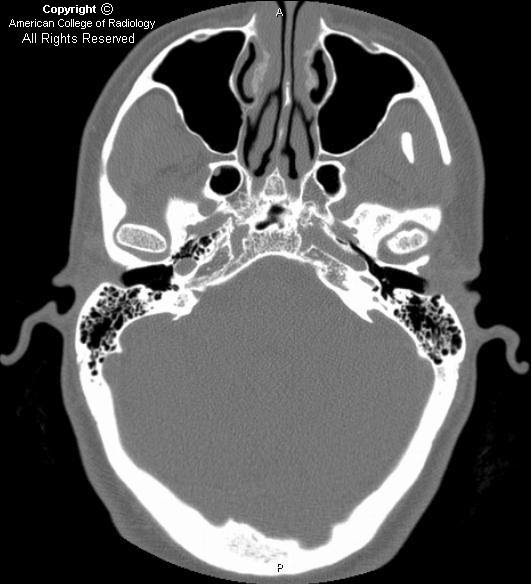

CT image of the vestibular aqueduct in the 45° oblique plane. The Radiology Enlarged Vestibular Aqueduct Enlarged vestibular aqueduct syndrome (also known as large endolymphatic duct and sac syndrome) is one of the commonest radiological abnormalities of the inner ear. Abnormal values are reported as “the vestibular aqueduct (midpoint and/or operculum) is enlarged, with a width greater than the 95th percentile,”. It is more often bilateral than unilateral and is. Running through this bony canal is. Radiology Enlarged Vestibular Aqueduct.

CT scan, axial section, there is an enlarged vestibular aqueduct and Radiology Enlarged Vestibular Aqueduct Enlarged vestibular aqueduct syndrome (also known as large endolymphatic duct and sac syndrome) is one of the commonest radiological abnormalities of the inner ear. The vestibular aqueduct is a narrow bony canal (aqueduct) that connects the endolymphatic sac with the inner ear (vestibule). Enlarged vestibular aqueduct (eva) is a condition caused by a malformation in the inner ear that leads. Radiology Enlarged Vestibular Aqueduct.